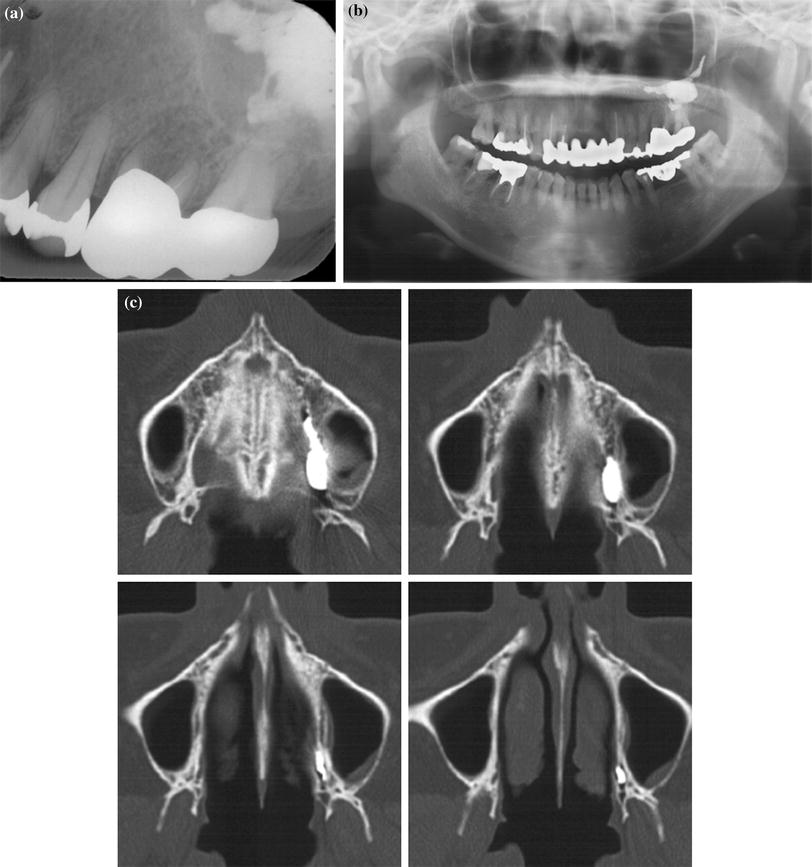

From www.researchgate.net

(PDF) Endodontic management of maxillary first molar with 7 root canals How Is Root Canal Diagnosed Read about root canal cost, pain, symptoms, signs, and recovery. why does tooth pulp need to be removed? a root canal (endodontic therapy) is a dental treatment for infections in tooth pulp, the innermost layer of your teeth. root canal treatment is usually successful at saving the tooth and clearing the infection. What are the signs that. How Is Root Canal Diagnosed.

Figure 1 from Maxillary first molar with seven root canals diagnosed How Is Root Canal Diagnosed a root canal (endodontic therapy) is a dental treatment for infections in tooth pulp, the innermost layer of your teeth. a root canal is performed when the endodontist removes the infected pulp and nerve in the root of the tooth, cleans and. Learn about the root canal procedure. human teeth may have one to four root canals,. How Is Root Canal Diagnosed.

Figure 2 from Endodontic Management of Maxillary First Molar with Seven How Is Root Canal Diagnosed human teeth may have one to four root canals, depending on the anatomy of the tooth. a root canal is performed when the endodontist removes the infected pulp and nerve in the root of the tooth, cleans and. Read about root canal cost, pain, symptoms, signs, and recovery. root canal treatment (endodontics) is a dental procedure used. How Is Root Canal Diagnosed.

Figure 2 from Maxillary first molar with seven root canals diagnosed How Is Root Canal Diagnosed why does tooth pulp need to be removed? Read about root canal cost, pain, symptoms, signs, and recovery. a root canal is performed when the endodontist removes the infected pulp and nerve in the root of the tooth, cleans and. a root canal (endodontic therapy) is a dental treatment for infections in tooth pulp, the innermost layer. How Is Root Canal Diagnosed.